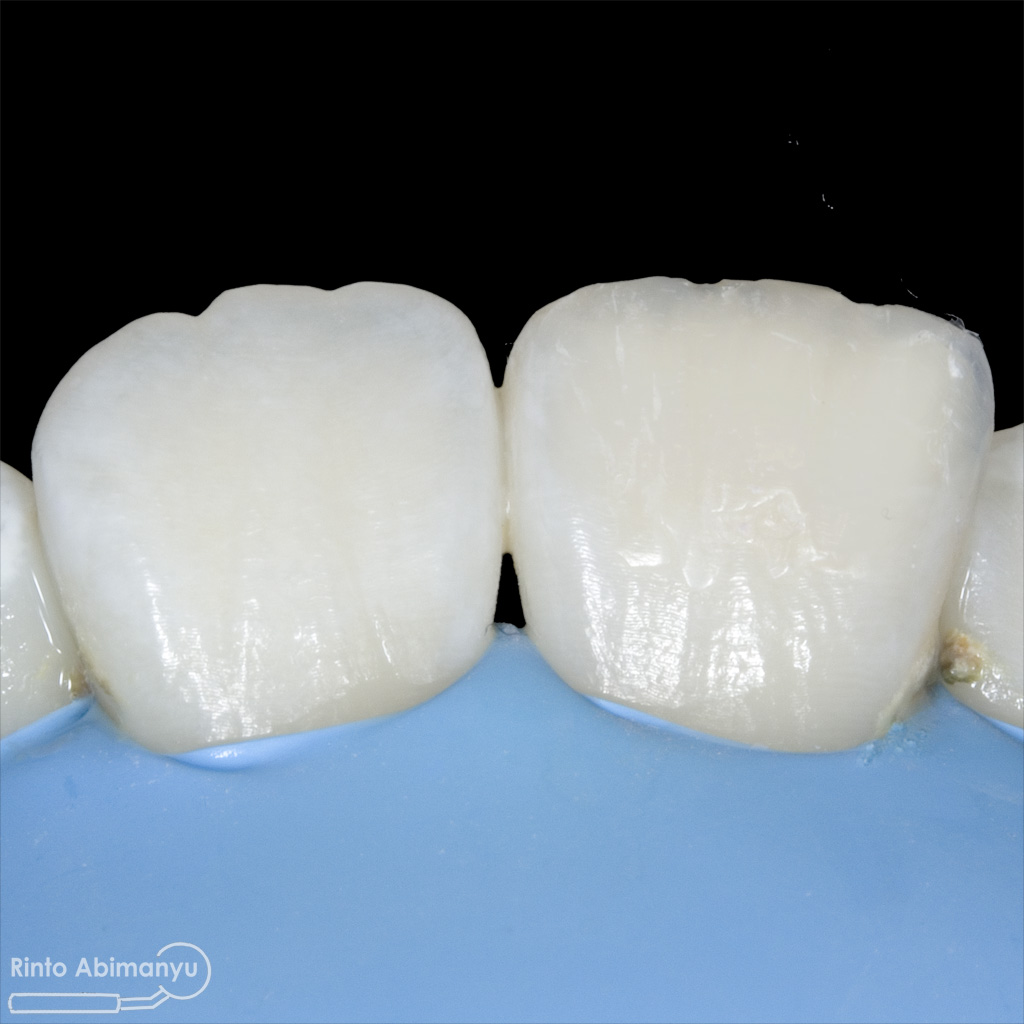

Pertama saya lakukan anestesi infiltrasi dan kemudian memasang rubber dam untuk isolasi daerah kerja, dilanjutkan pembersihan karies dan pembukaan kamar pulpa.. Pada kasus ini pengerjaan dilakukan langsung pada dua gigi…

Setalah pengisian usahakan kamar pulpa dibersihkan dari sisa2 siler dan kotoran2 agar bahan adhesive yang kita pakai untuk restorasi dapat melekat maksimal.. Untuk basis saya menggunakan X-tra Base (Voco) kemudian diatasnya memakai komposit Z 350 XT (3M)…